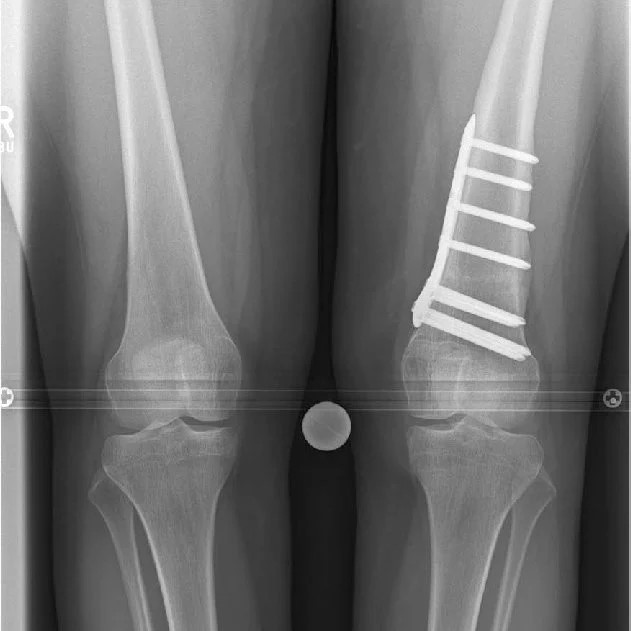

Bow legs, also known as genu varum, is a condition where the legs appear bowed outwards when standing. This condition can cause discomfort, pain, and even difficulty walking. In severe cases, surgery may be required to correct the alignment of the legs. In this article, we will discuss the causes, symptoms, and treatment options for bow legs, including the various surgical procedures available.

A doctor can diagnose bow legs by performing a physical examination and assessing the alignment of the legs. Imaging tests such as X-rays or MRI scans may also be used to confirm the diagnosis.